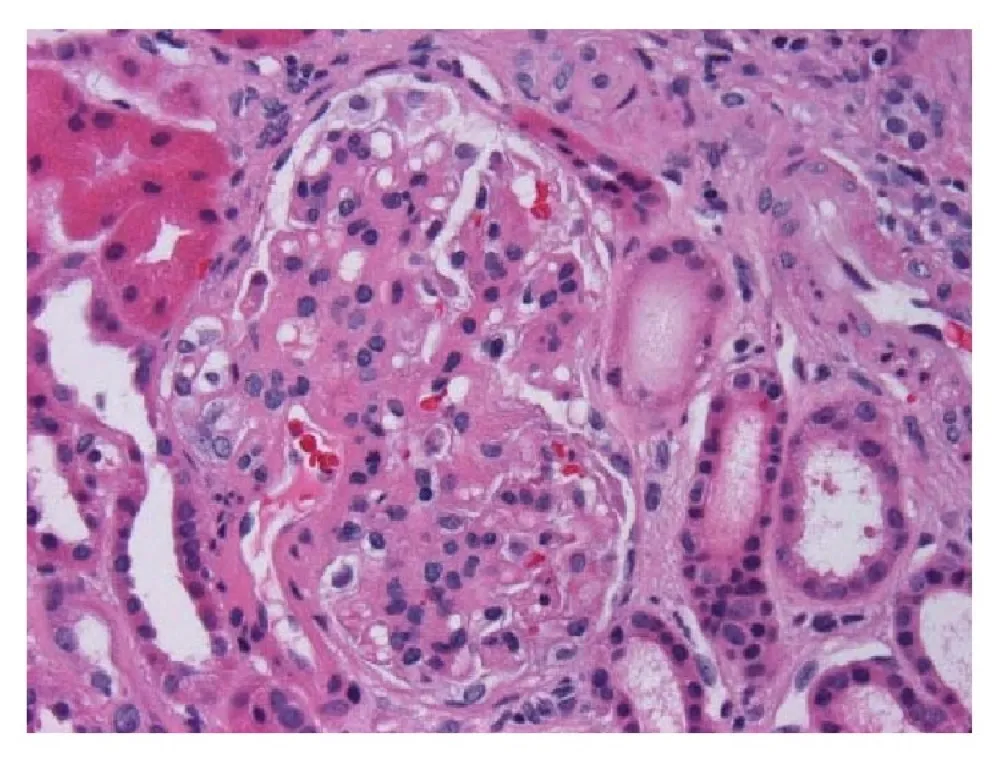

Injúria Renal Aguda (revisão Lancet 2025)

Injúria Renal Aguda (revisão Lancet 2025)